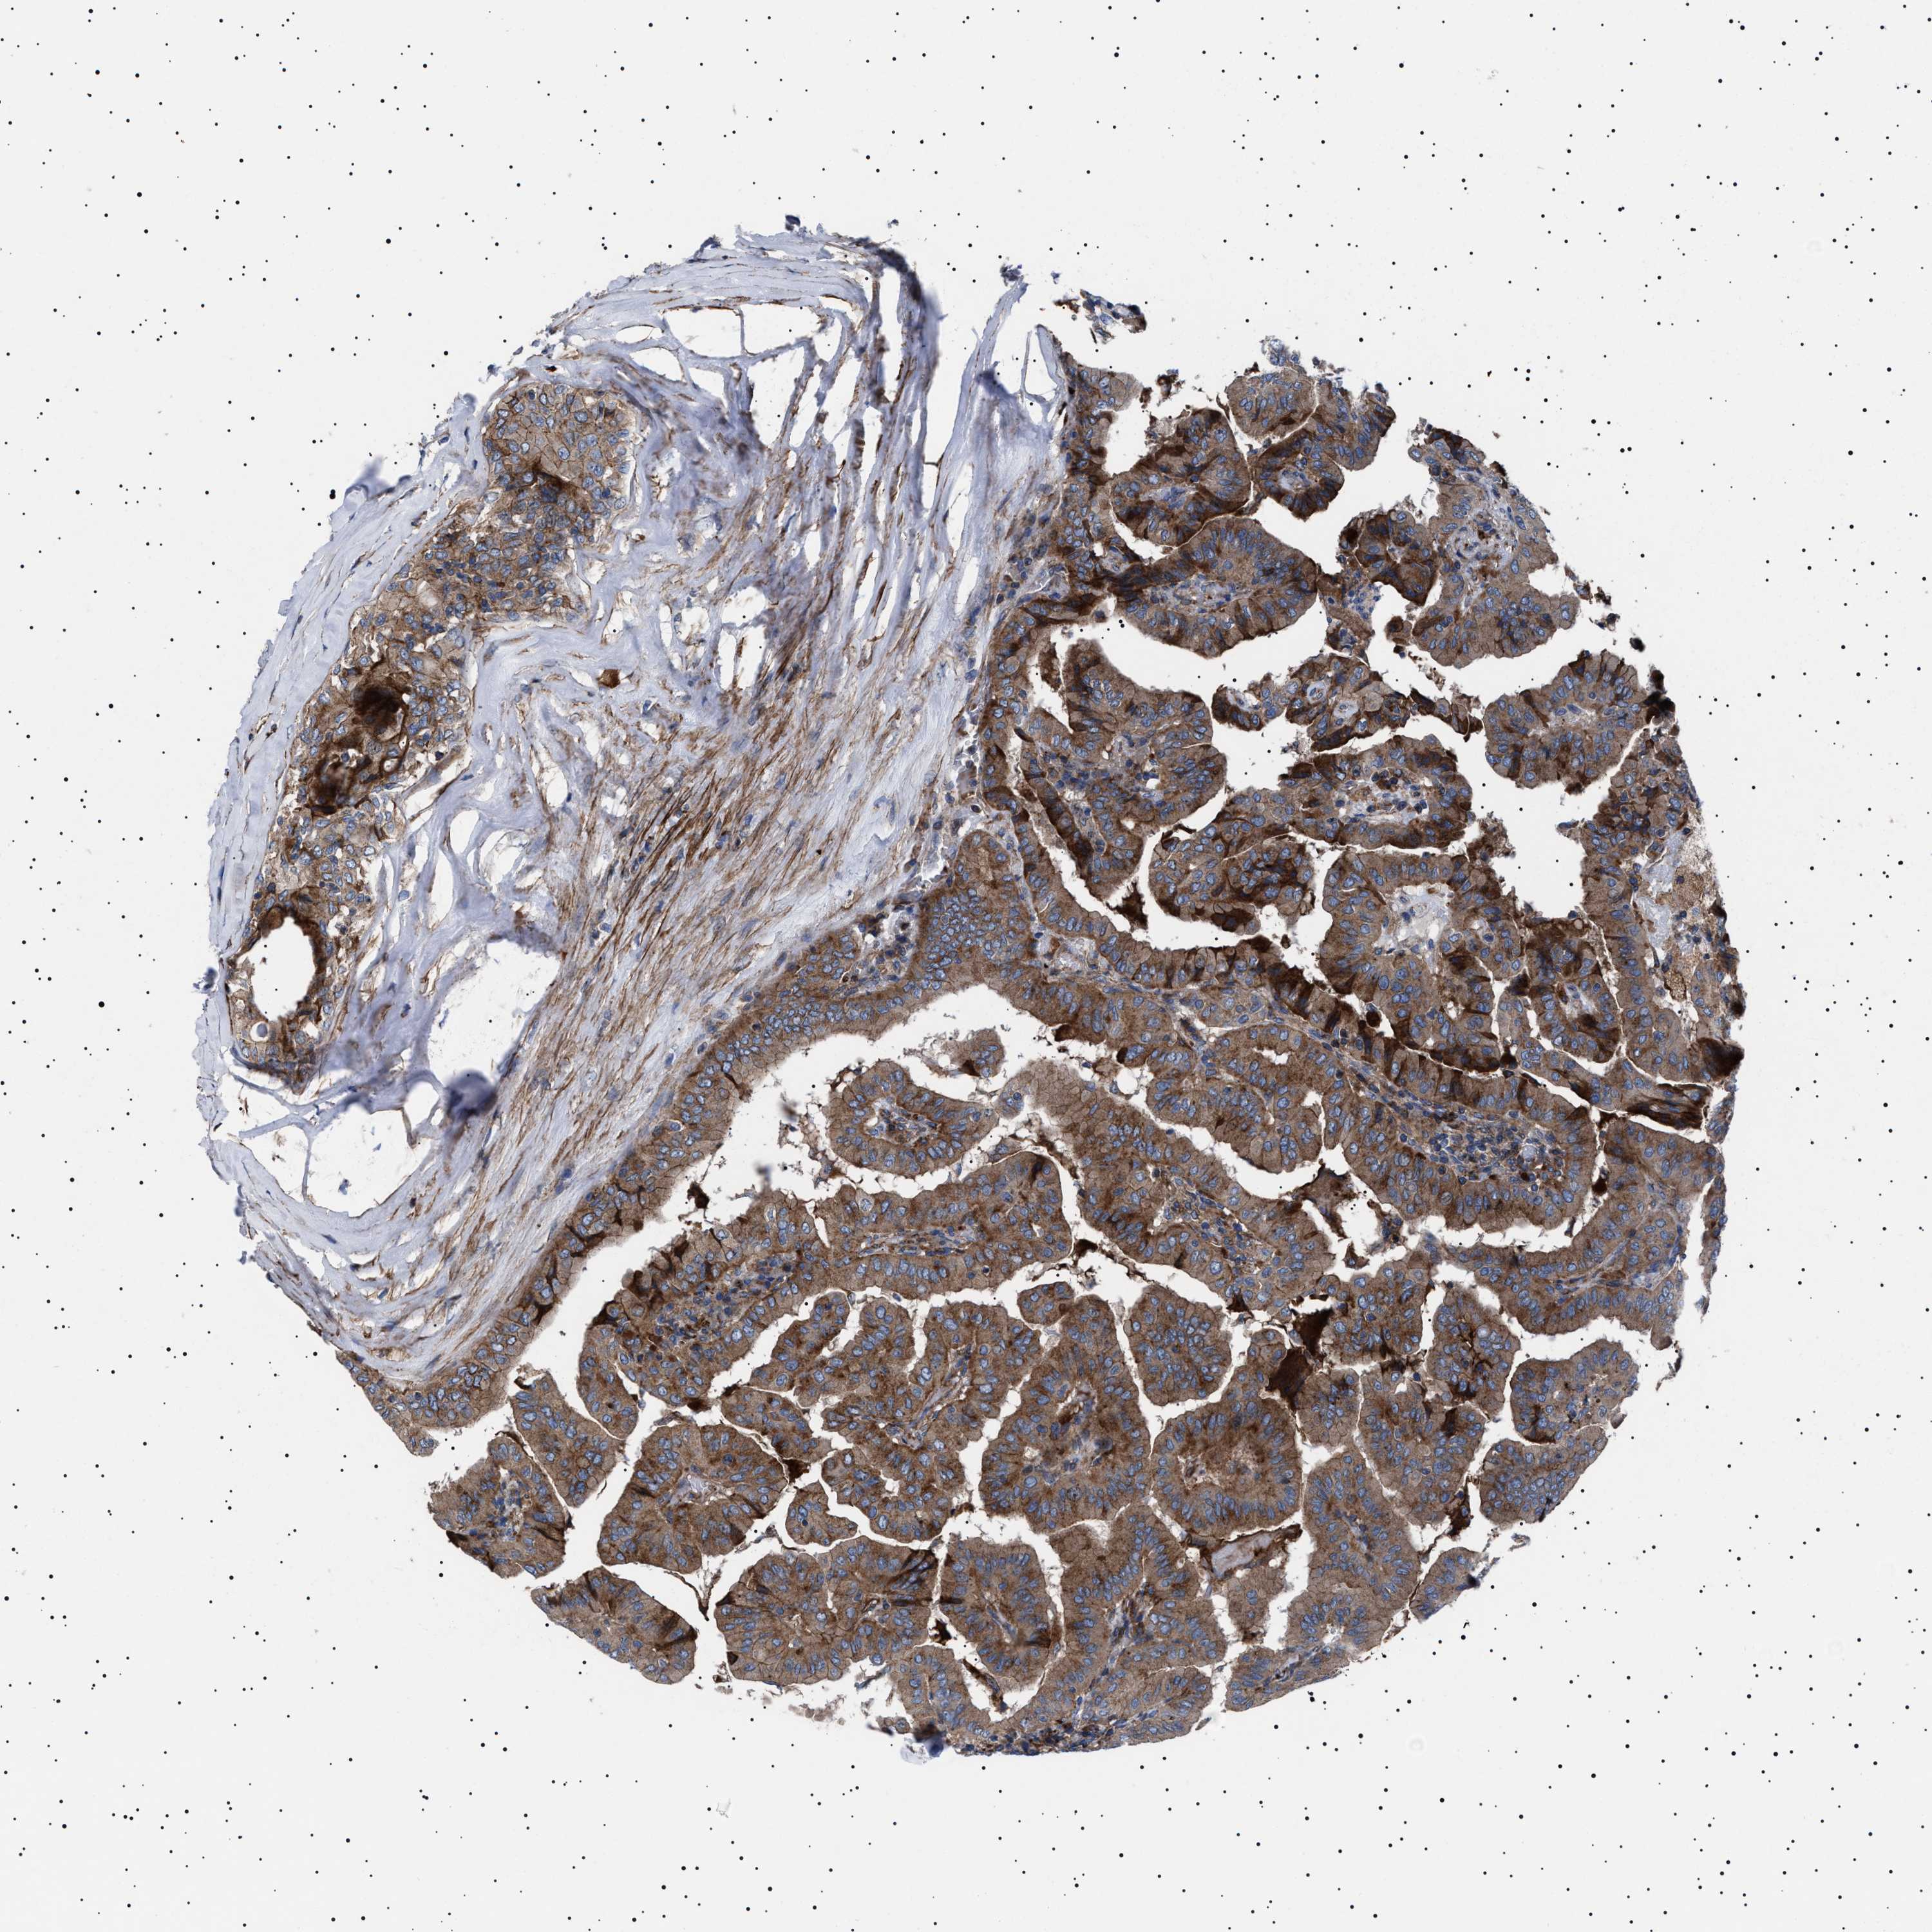

THYROID CANCER - Protein expressioni

A mouse-over function shows sample information and annotation data. Click on an image to view it in a full screen mode. Samples can be filtered based on level of antibody staining by selecting one or several of the following categories: high, medium, low and not detected. The assay and annotation is described here.

Note that samples used for immunohistochemistry by the Human Protein Atlas do not correspond to samples in the TCGA dataset.

Antibody stainingi

Antibody staining in the annotated cell types in the current human tissue is reported as not detected, low, medium, or high, based on conventional immunohistochemistry profiling in selected tissues. This score is based on the combination of the staining intensity and fraction of stained cells.

Each image is clickable and will lead to virtual microscopy that enables deeper exploration of all samples and also displays staining intensity scores, fraction scores and subcellular localization as well as patient and tissue information for each sample.

Antibody HPA015634

Antibody HPA021506

Staining

High

Medium

Low

Not detected

Intensity

Strong

Moderate

Weak

Negative

Quantity

>75%

75%-25%

<25%

None

Location

Nuclear

Cytoplasmic/membranous

Cytoplasmic/membranous,nuclear

Papillary adenocarcinoma, NOS

Follicular adenoma carcinoma, NOS